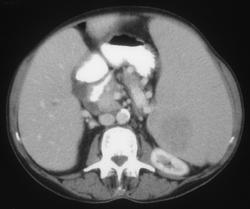

Splenic Infarction